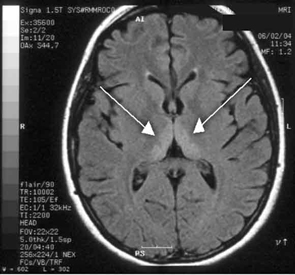

Haematological and biochemical test results were largely normal, but her serum levels of creatinine (0.04 mmol/L; normal range [NR], 0.05–0.10 mmol/L) and urea (2.2 mmol/L; NR, 2.5–6.1 mmol/L) were slightly low, and her INR (international normalised ratio) was 2.0 (NR, 0.8–1.2). There were also some elevated levels in her liver function test results: γ-glutamyl transferase, 60 U/L (NR, < 50 U/L); alanine aminotransferase, 486 U/L (NR, < 55 U/L); and bilirubin, 32 U/L (NR, 0–19 U/L). Cerebrospinal fluid (CSF) examination and magnetic resonance imaging (MRI) were also undertaken to exclude intracranial causes. The CSF findings were normal, but the MRI revealed bilateral thalamic lesions (Figure 2).